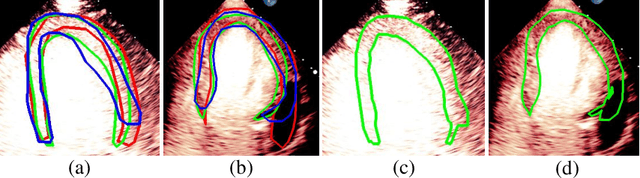

Most existing deep learning-based frameworks for image segmentation assume that a unique ground truth is known and can be used for performance evaluation. This is true for many applications, but not all. Myocardial segmentation of Myocardial Contrast Echocardiography (MCE), a critical task in automatic myocardial perfusion analysis, is an example. Due to the low resolution and serious artifacts in MCE data, annotations from different cardiologists can vary significantly, and it is hard to tell which one is the best. In this case, how can we find a good way to evaluate segmentation performance and how do we train the neural network? In this paper, we address the first problem by proposing a new extended Dice to effectively evaluate the segmentation performance when multiple accepted ground truth is available. Then based on our proposed metric, we solve the second problem by further incorporating the new metric into a loss function that enables neural networks to flexibly learn general features of myocardium. Experiment results on our clinical MCE data set demonstrate that the neural network trained with the proposed loss function outperforms those existing ones that try to obtain a unique ground truth from multiple annotations, both quantitatively and qualitatively. Finally, our grading study shows that using extended Dice as an evaluation metric can better identify segmentation results that need manual correction compared with using Dice.